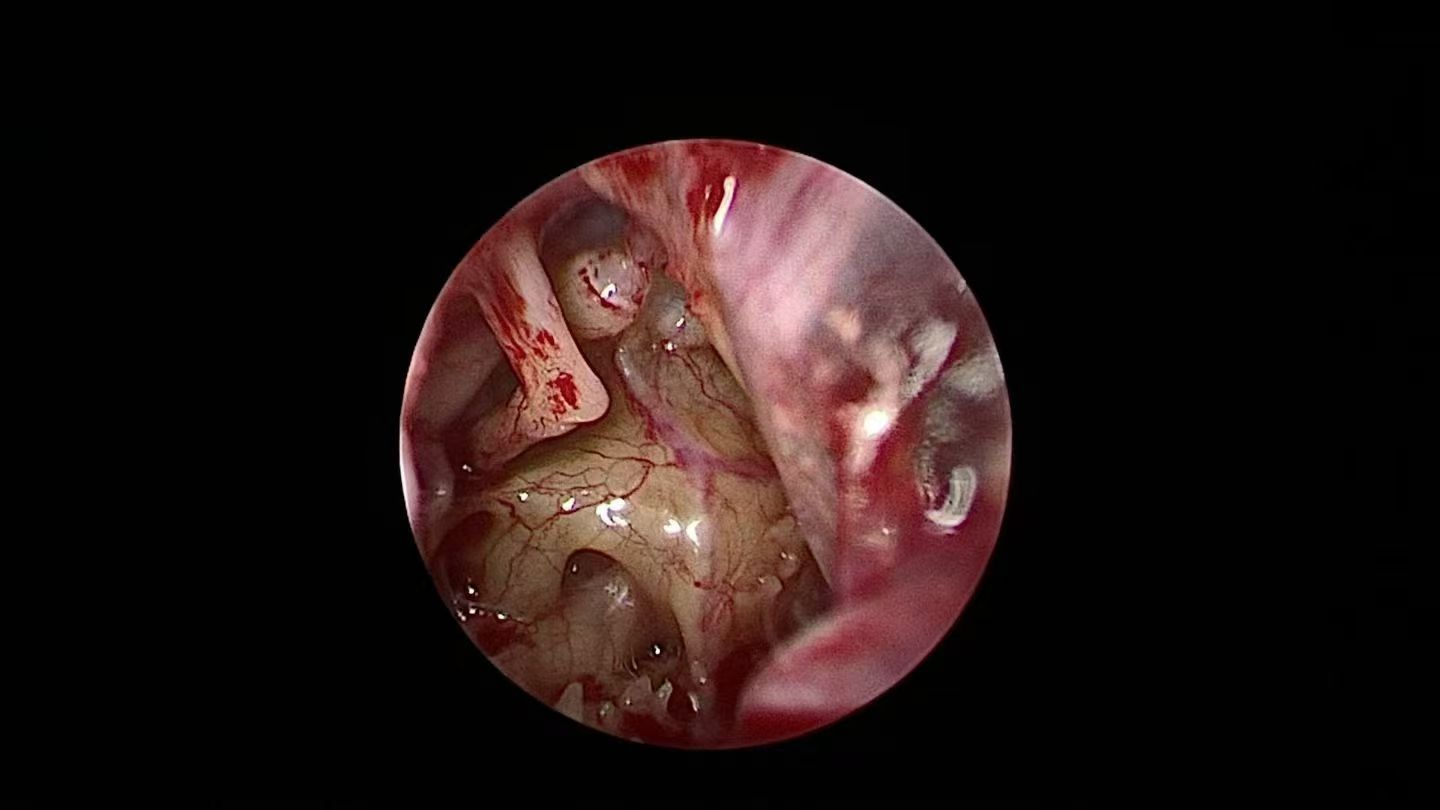

“手术?会不会很危险?要在耳朵上开大口子吗?”面对李女士的担忧,冷辉教授团队给出了定心丸:“这是一种超微创手术,仅在耳道内放入精细的耳内镜,借助屏幕放大的视野,精准切断鼓膜张肌肌腱和镫骨肌肌腱,从根源上阻断眩晕,同时对前庭症状和听力症状产生积极影响。而且手术时间短、出血量少、体表没有任何切口,术后恢复快。”

术中暴露手术视野

切断镫骨肌肌腱和鼓膜张肌肌腱